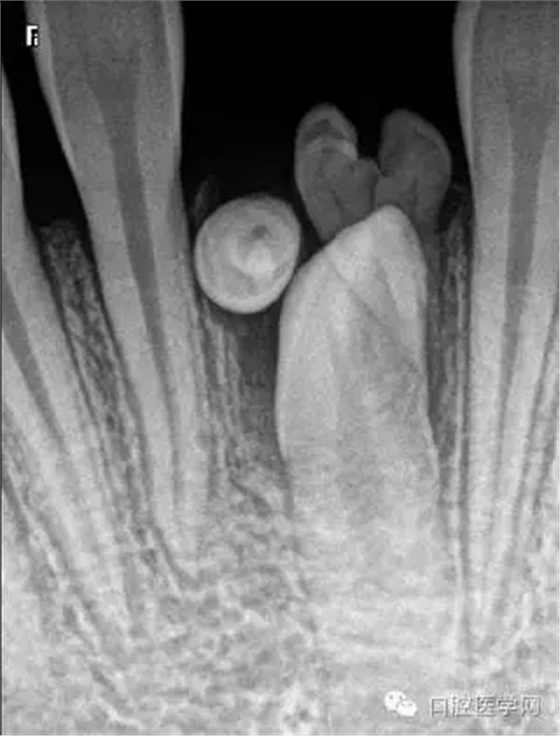

牙中牙

X線表現(xiàn):舌側(cè)窩陷入過(guò)深,形似一小牙包于牙髓中。